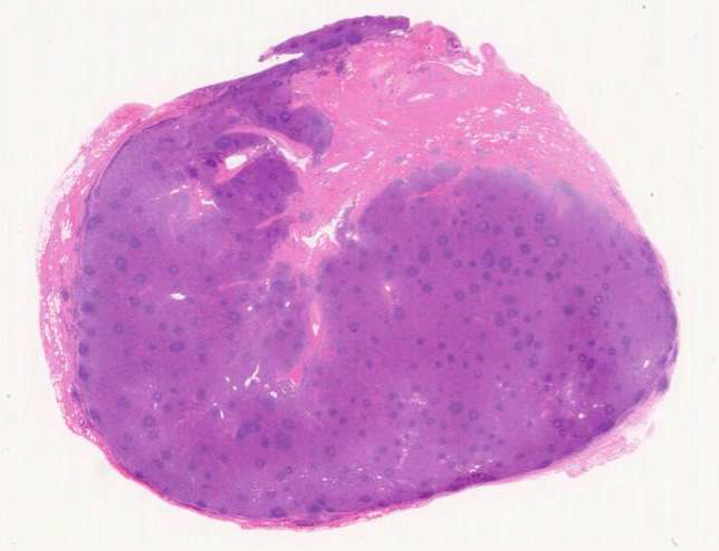

Castleman02.jpg

萎縮した濾胞がたくさん見られるリンパ節.

70歳男性

健康診断で腋窩リンパ節の腫大を指摘される。とくに症状はない。